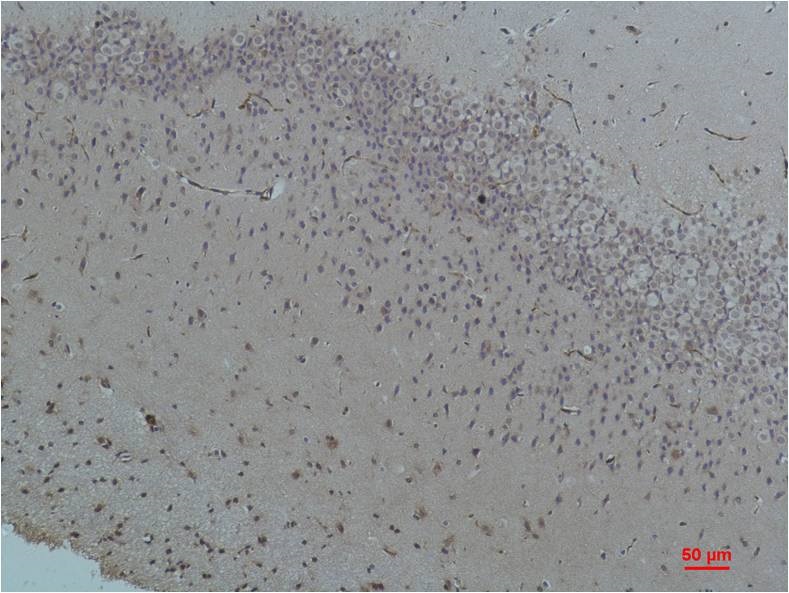

Immunohistochemical analysis of paraffin-embedded Rat Brain Tissue using Bestrophin-1 (BE3450)Rabbit pAb diluted at 1:200